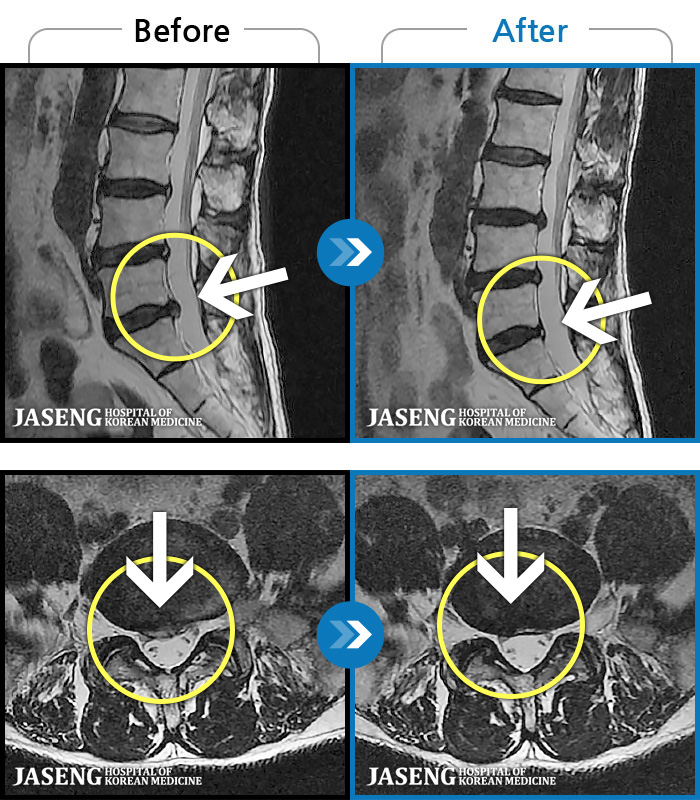

[ؿ] 23.09.18~25.01.27

ȯںп Ǹ ǿ ԿǾ, ο ġ ۿ Ƿ ġḦ Ͻñ ٶϴ.